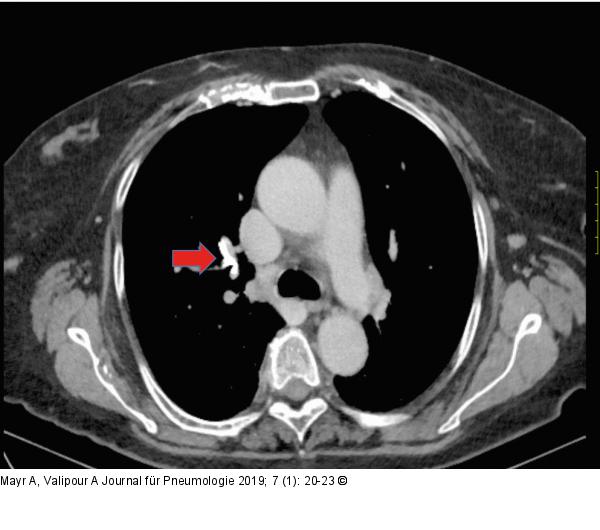

Abbildung 7: Thorax-CT

Thorax-CT